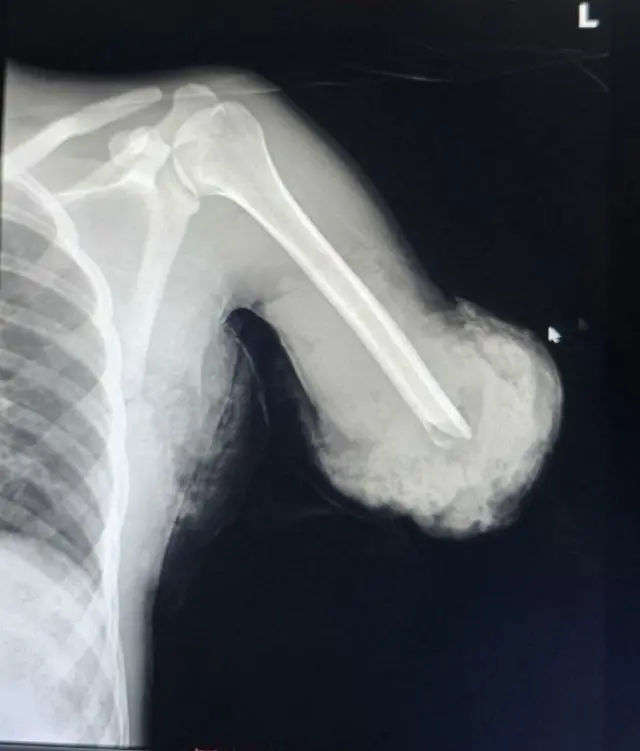

በድንገተኛ አደጋ ሙሉ በሙሉ የተቆረጠ የአንድ ወጣት ክንድ በቀዶ ሕክምና መግጠም እንደተቻለ የሳማሪታን የቀዶ ሕክምና ማዕከል ሜዲካል ዳይሬክተር ዶ/ር አንተነህ ካኽሉ ለቢቢሲ ገለጹ።

የ20 ዓመት ወጣት የሆነው ታካሚው ከሦስት ሳምንት በፊት የእንጨት መሰንጠቂያ ማሽን ላይ ሲሠራ እጁ ተቆርጦ ወደ ሆስፒታሉ መሄዱን ዶ/ር አንተነህ ገልጸዋል።

"ከክርኑ ከፍ ብሎ ነበር እጁ ተቆርጦ የመጣው። እጁ ከሰውነቱ ጋር ሙሉ በሙሉ ተለያየቶ ነበር" ብለዋል ሐኪሙ።

ሙሉ በሙሉ የተቆረጠ ክንድ በቀዶ ሕክምና መግጠም "መቶ ፐርሰንት እርግጠኛ ባልሆንም፣ ባለኝ መረጃ መሠረት ኢምፕላንቴሽን መሥራት ለአገራችን የመጀመሪያው ነው" ሲሉም ሜዲካል ዳይሬክተሩ ተናግረዋል።

ሐኪሙ የአንዳንድ ሰዎች ጣቶች ላይ የመቆረጥ አደጋ ሲያጋጥም 'ማይክሮ' [መለስተኛ] ቀዶ ሕክምና እንደሚደረግ ገልጸው፤ "ይሄኛው ግን ዋና ክንድ ነው ተቆርጦ የመጣው። ልጁ እና አካሉ ተለያይተው ነው የደረሱት" በማለት አብራርተዋል።